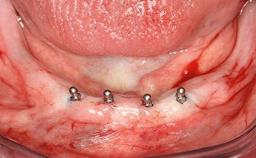

The patient presented with root fracture of the right central incisor with associated distal bone loss. After sectioning and extraction of the fractured root the distal papilla was lost, creating an esthetic compromise. This case demonstrates an option for treating this esthetic compromise. Early (Type 2) implant placement was performed at 7 weeks with simultaneous horizontal and vertical augmentation using Bio-Oss and Bio-Gide (Geistlich). After 3 months a connective tissue graft was performed at the time of implant exposure. Despite these surgical procedures, the papilla could not be recovered. As a result, a prosthetic solution was necessary.